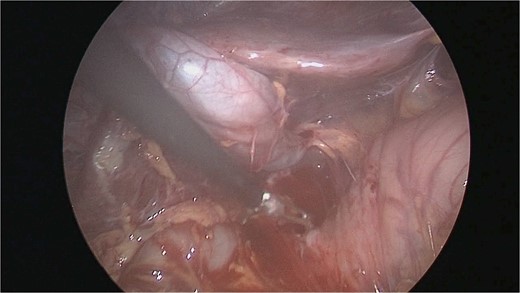

There were extensive perihepatic adhesions with involvement of the subhepatic space (Fig. 3). The initial intraoperative assessment was that this inflammation was secondary to a prior cholecystitis, but subsequent dissection revealed a pristine gallbladder (Fig. 4) with inflammatory adhesions in the pyloro-duodenal region (Fig. 5). All adhesions encasing the duodenum were lysed and the duodenum was kockerized (Fig. 6).

Extensive supra- and subhepatic adhesions were noted at laparoscopy.